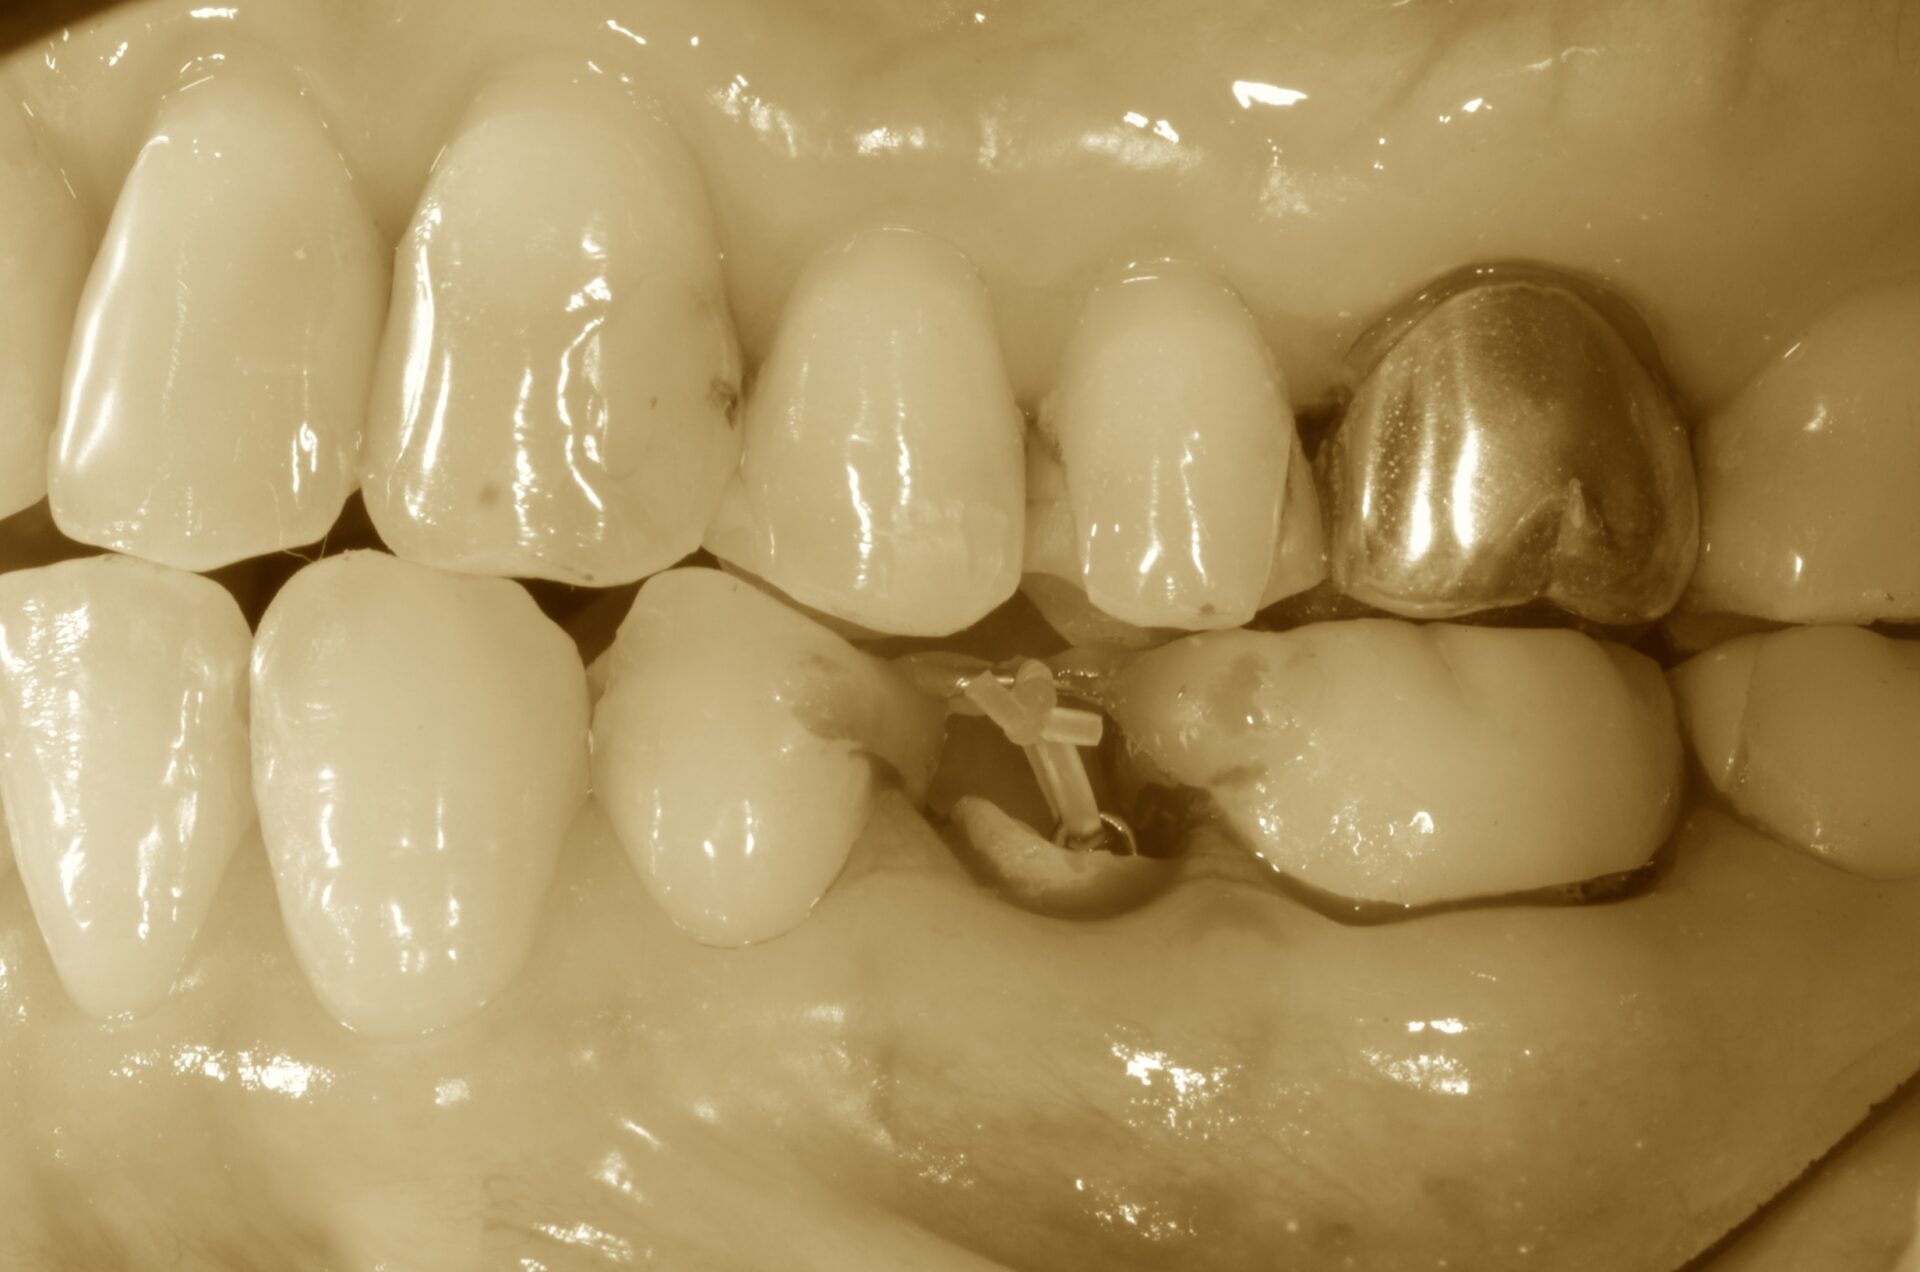

牽引開始